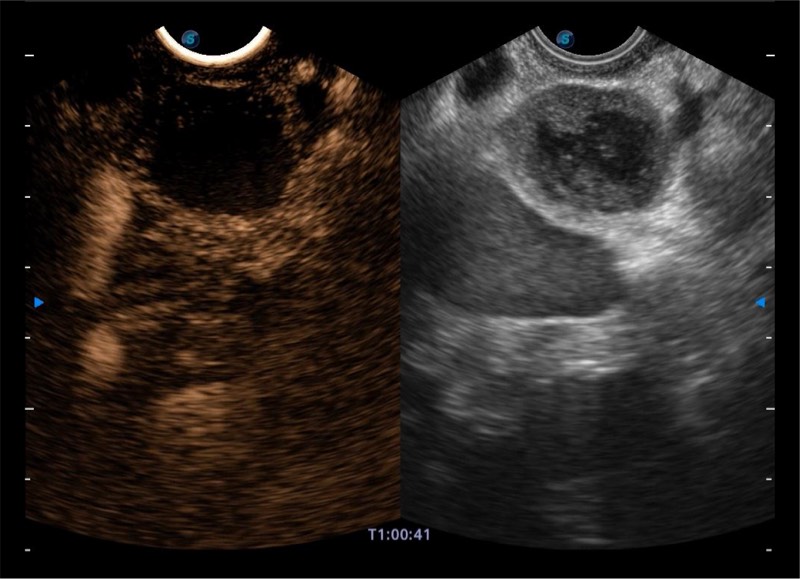

基于二十年的超声技术积累,环球UG官网提供了最新一代的独立超声主机,在提供高质量图像的同时满足多学科使用。具备常见多普勒技术并提供弹性成像、声学造影等高端影像技术。新一代传感器具有更强的抗干扰能力并减少图像伪影。

4-12MHZ宽频输出